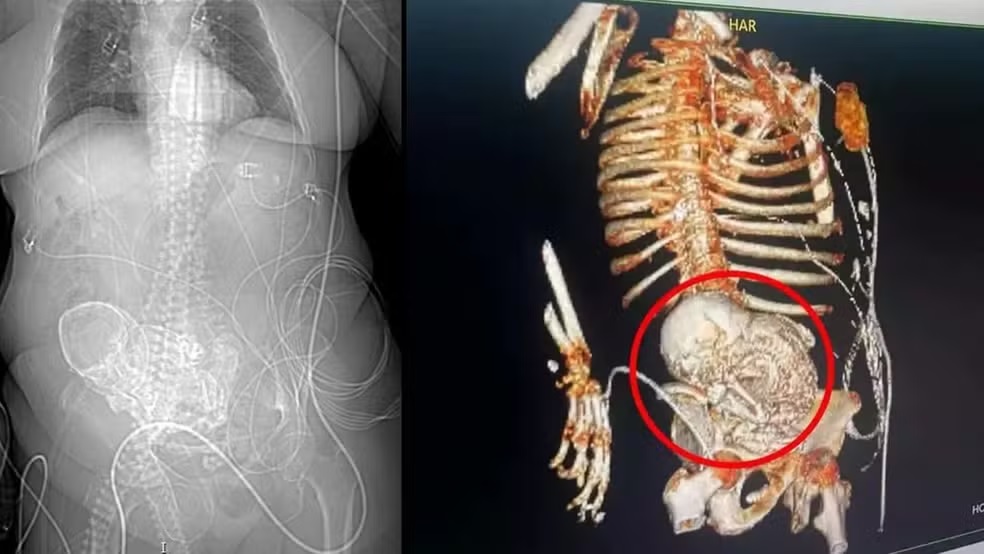

O feto calcificado, cuja suspeita de médicos é que tenha passado cinco décadas no abdômen de paciente do Hospital Regional de Ponta Porã (MS), seria irmão de sete – seis mulheres e um homem –, tio de 30 crianças, adolescentes e adultos, e tio-avô de 5. Descoberto durante tomografia computadorizada, feita para verificar qual o motivo das dores que idosa de 81 anos sentia, o bebê “litopédio”, como é chamado na Medicina, era filho da dona de casa Daniela Almeida Vera.

Uma idosa, de 81 anos, descobriu que carregava um "bebê de pedra", ao ser encaminhada para o Hospital Regional de Ponta Porã, na região sul de Mato Grosso do Sul, com dores abdominais, de acordo com as informações do secretário de saúde da cidade, Patrick Derzi.

Idosa morreu após descobrir bebê calcificado em abdômen — Foto: Reprodução

A suspeita da equipe médica é de que a mulher estava com o feto calcificado no abdômen há 56 anos, desde quando a idosa teve a última gestação. A idosa morreu logo após cirurgia para retirada do feto.